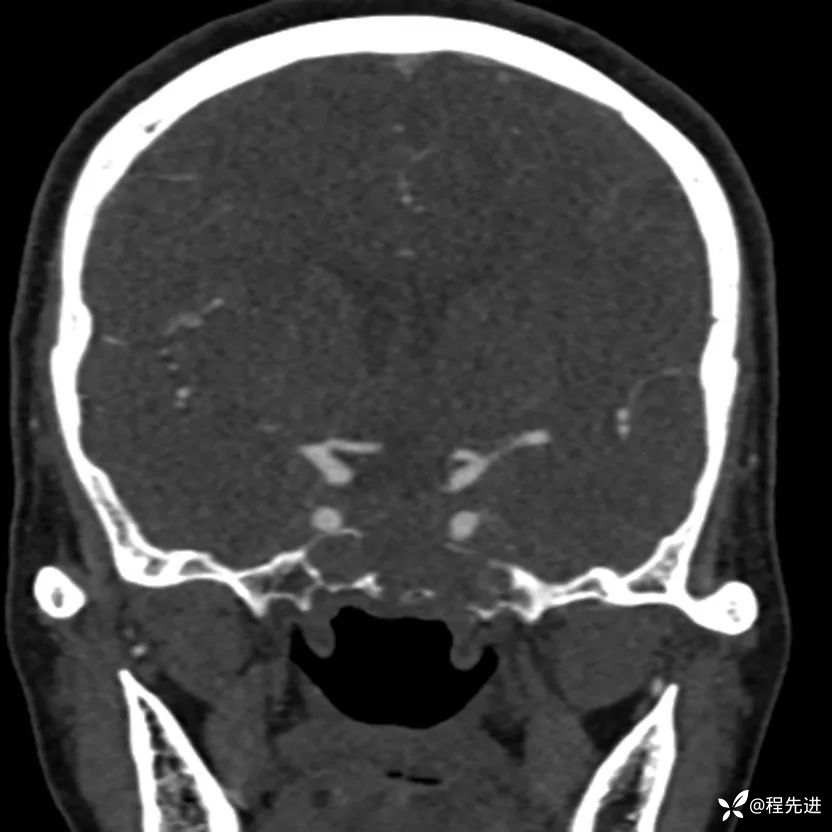

简要病史:外伤检查发现颅底占位

CT增强: